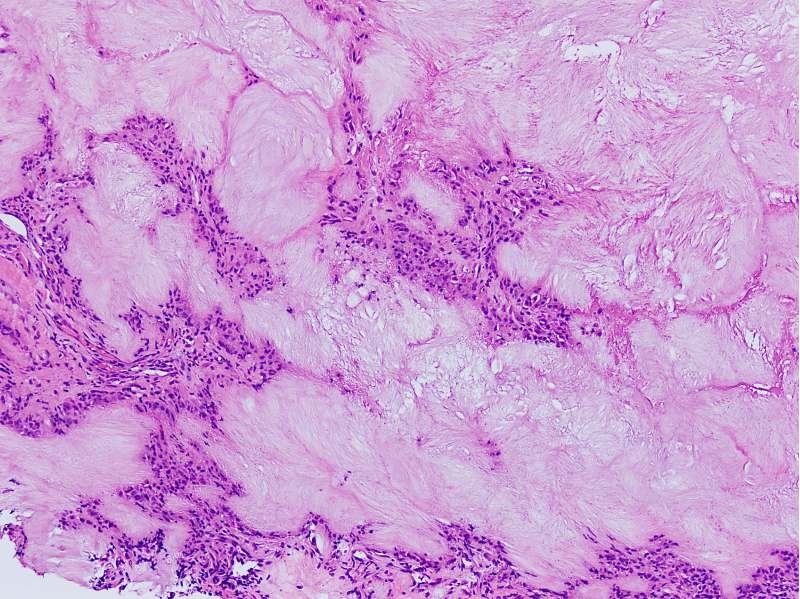

Microscopic (histologic) description

- Gout tophus:

- Nodular aggregates / granuloma-like appearance consisting of acellular, amorphous, pale eosinophilic material surrounded by palisading arrangement of histiocytes and multinucleated giant cells (Dermatol Online J 2015;21:13030)

- Feathery appearance in some deposits due to empty needle shaped spaces (Skeletal Radiol 2020;49:1325)

- Presence of monosodium urate crystals (MSU) is diagnostic

- Needle-like crystals that measure 5 - 25 micrometers in length

- Brightly anisotropic under polarized light

- Negative birefringence when examined with an interference plate in the light path (Otol Neurotol 2009;30:127)

- Crystals appear yellowish when aligned parallel to the plate axis

- Bluish appearance when alignment is across the direction of polarization

Microscopic (histologic) images